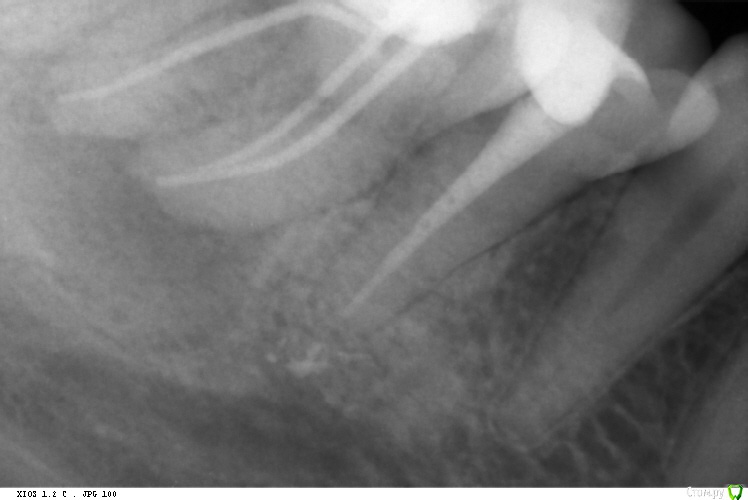

St. Опубликовано 3 декабря, 2015 Автор Поделиться Опубликовано 3 декабря, 2015 Пациентка, 28лет. Зуб ранее лечен по поводу неосложненного кариеса около 8 лет назад, пломба состоятельная. Полгода назад на ОПГ обнаружен очаг разрежения, свищ по переходной складке. Субъективно жалоб не было. Сделали КТ. Обсудили возможности и риски эндо.Пациентка согласилась попробовать консервативное лечение, но только позже. В первый визит свищ с экссудатом, перкуссия слабо положительная. Открыли, трещин нет, каналы широкие, некротические массы, специфический запах. ПроТейперы Ф1, апикально 35.02 .Медобработка гипохлорит(+ у/з), эдта. Кальций. Временная пломба. Через 10 дней симптоматики нет, экссудата из свища нет, однако свищ сохраняется.Ещё раз мех и мед обработка. Гидроокись. Пациентка уехала на месяц. Визит третий. Свищ закрылся. Перкуссиб б/б.Расширила апикально до 45.02. Мед.обработка гипохлорит, ЭДТА, перекись, хлоргексидин 2%. Латералка. Ждем что будет через 6 мес. 1 Ссылка на комментарий